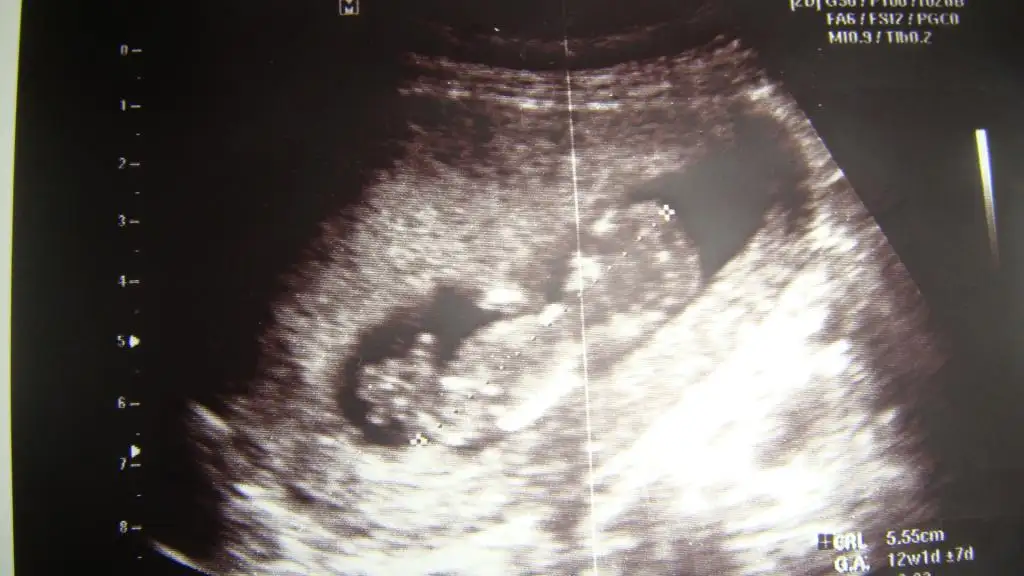

dr soylemeden siz gorun genital nub teorisi ( bebegin cinsiyeti)

ben de yorumları alabilir miyim? (doktorum bir tahminde bulundu net olmamakla birlikte ve ben de konuyla ilgili açıklamaları okuyunca bir yorum yapabiliyorum ama bakalım sizler ne diyeceksiniz?) :34:

orası ne kadar girintili çıkıntılı. tam anlayamadım ayak mı nub çıkıntısı mı?erkek gibi ama ORKDM gelsin bakalım ne diycek?

nuba bakarak ama sua var bebegin beli duz mu once ona bak degilse duzmus gibi gozunle yap sonra belinden bir cizgi cek birde cikintinin hizasindan sonuca bak paralelse kiz

dikeyse erkek

paralel derken daha aşağıya doğru bakan nub kız daha dik duran erkek gibide denilebilirmi???

oy oy bu geometri gibi resmen canım,paralel dik anlıyorum da hangisi nub hangisi bacak,kordon ayırt edemiyorum:26: